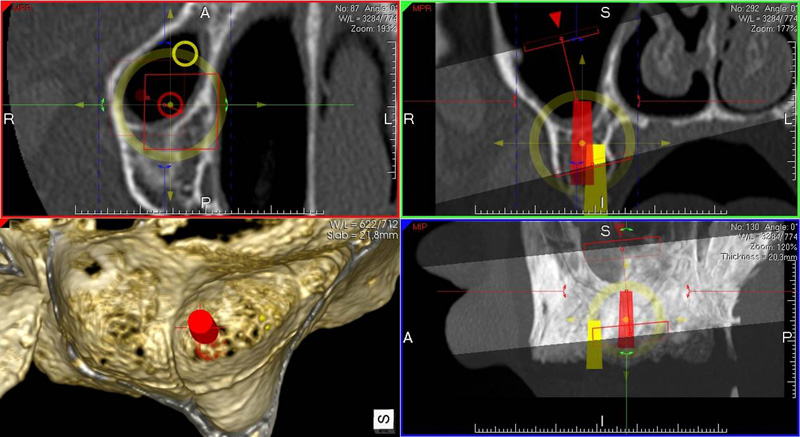

Pro následné plánování využíváme počítačové programy NewTom Implant Planning a coDiagnostiX, které slouží na plánování vhodných pozic pro zavedení implantátů, operačních šablon, kostních bloků, pozdějších protetických náhrad, ...

- operace pomocí OP šablon. Ve speciálním programu coDiagnostiX se využívají data z CB CT scanu - tedy údaje o množství a kvalitě kosti, dále data získaná ze scanu modelu čelistí s modelem plánované protetické náhrady (korunky, můstku…)

- tedy údaje tloušťce sliznice, pozice a tvaru náhrady.

Tím máme všechny potřebné údaje pro plánování pozic implantátů, jejich potřebné délce a průměru. Abychom mohli implantáty zavést do naplánovaných pozic v ústech pacienta, umožňuje tento program vymodelovat speciální operační šablonu, která je zhotovena 3D tiskárnou. Pomocí této šablony, která se umístí do úst pacienta, pak probíhá vlastní operace

- zavádění implantátů.

Lékař si vytvoří všechny typy zobrazení potřebných pro naplánování – tedy 2D snímky (panoramatický), příčné řezy i 3D model.

Vidí zde i důležité anatomické útvary – čelistní dutinu, průběh nervu atd. Po proměření množství kosti – šířky i výšky vybere z databáze vhodný typ implantátu a umístí ho do požadované lokality.

Ihned vidí jeho pozici ve všech 3 rovinách a na všech snímcích i 3D modelu. Může upravovat podle potřeby jeho pozici, sklon atd.

Tento program umožňuje tříprostorovou počítačovou simulaci při plánování pozic implantátů. Součástí programu je i databáze, ve které mohou být uloženy všechny typy implantátů od všech výrobců, včetně jejich délek, průměrů i tvarů.

Vidí zde i důležité anatomické útvary – čelistní dutinu, průběh nervu atd. Po proměření množství kosti – šířky i výšky vybere z databáze vhodný typ implantátu a umístí ho do požadované lokality. Ihned vidí jeho pozici ve všech 3 rovinách a na

všech snímcích i 3D modelu. Může upravovat podle potřeby jeho pozici, sklon atd.